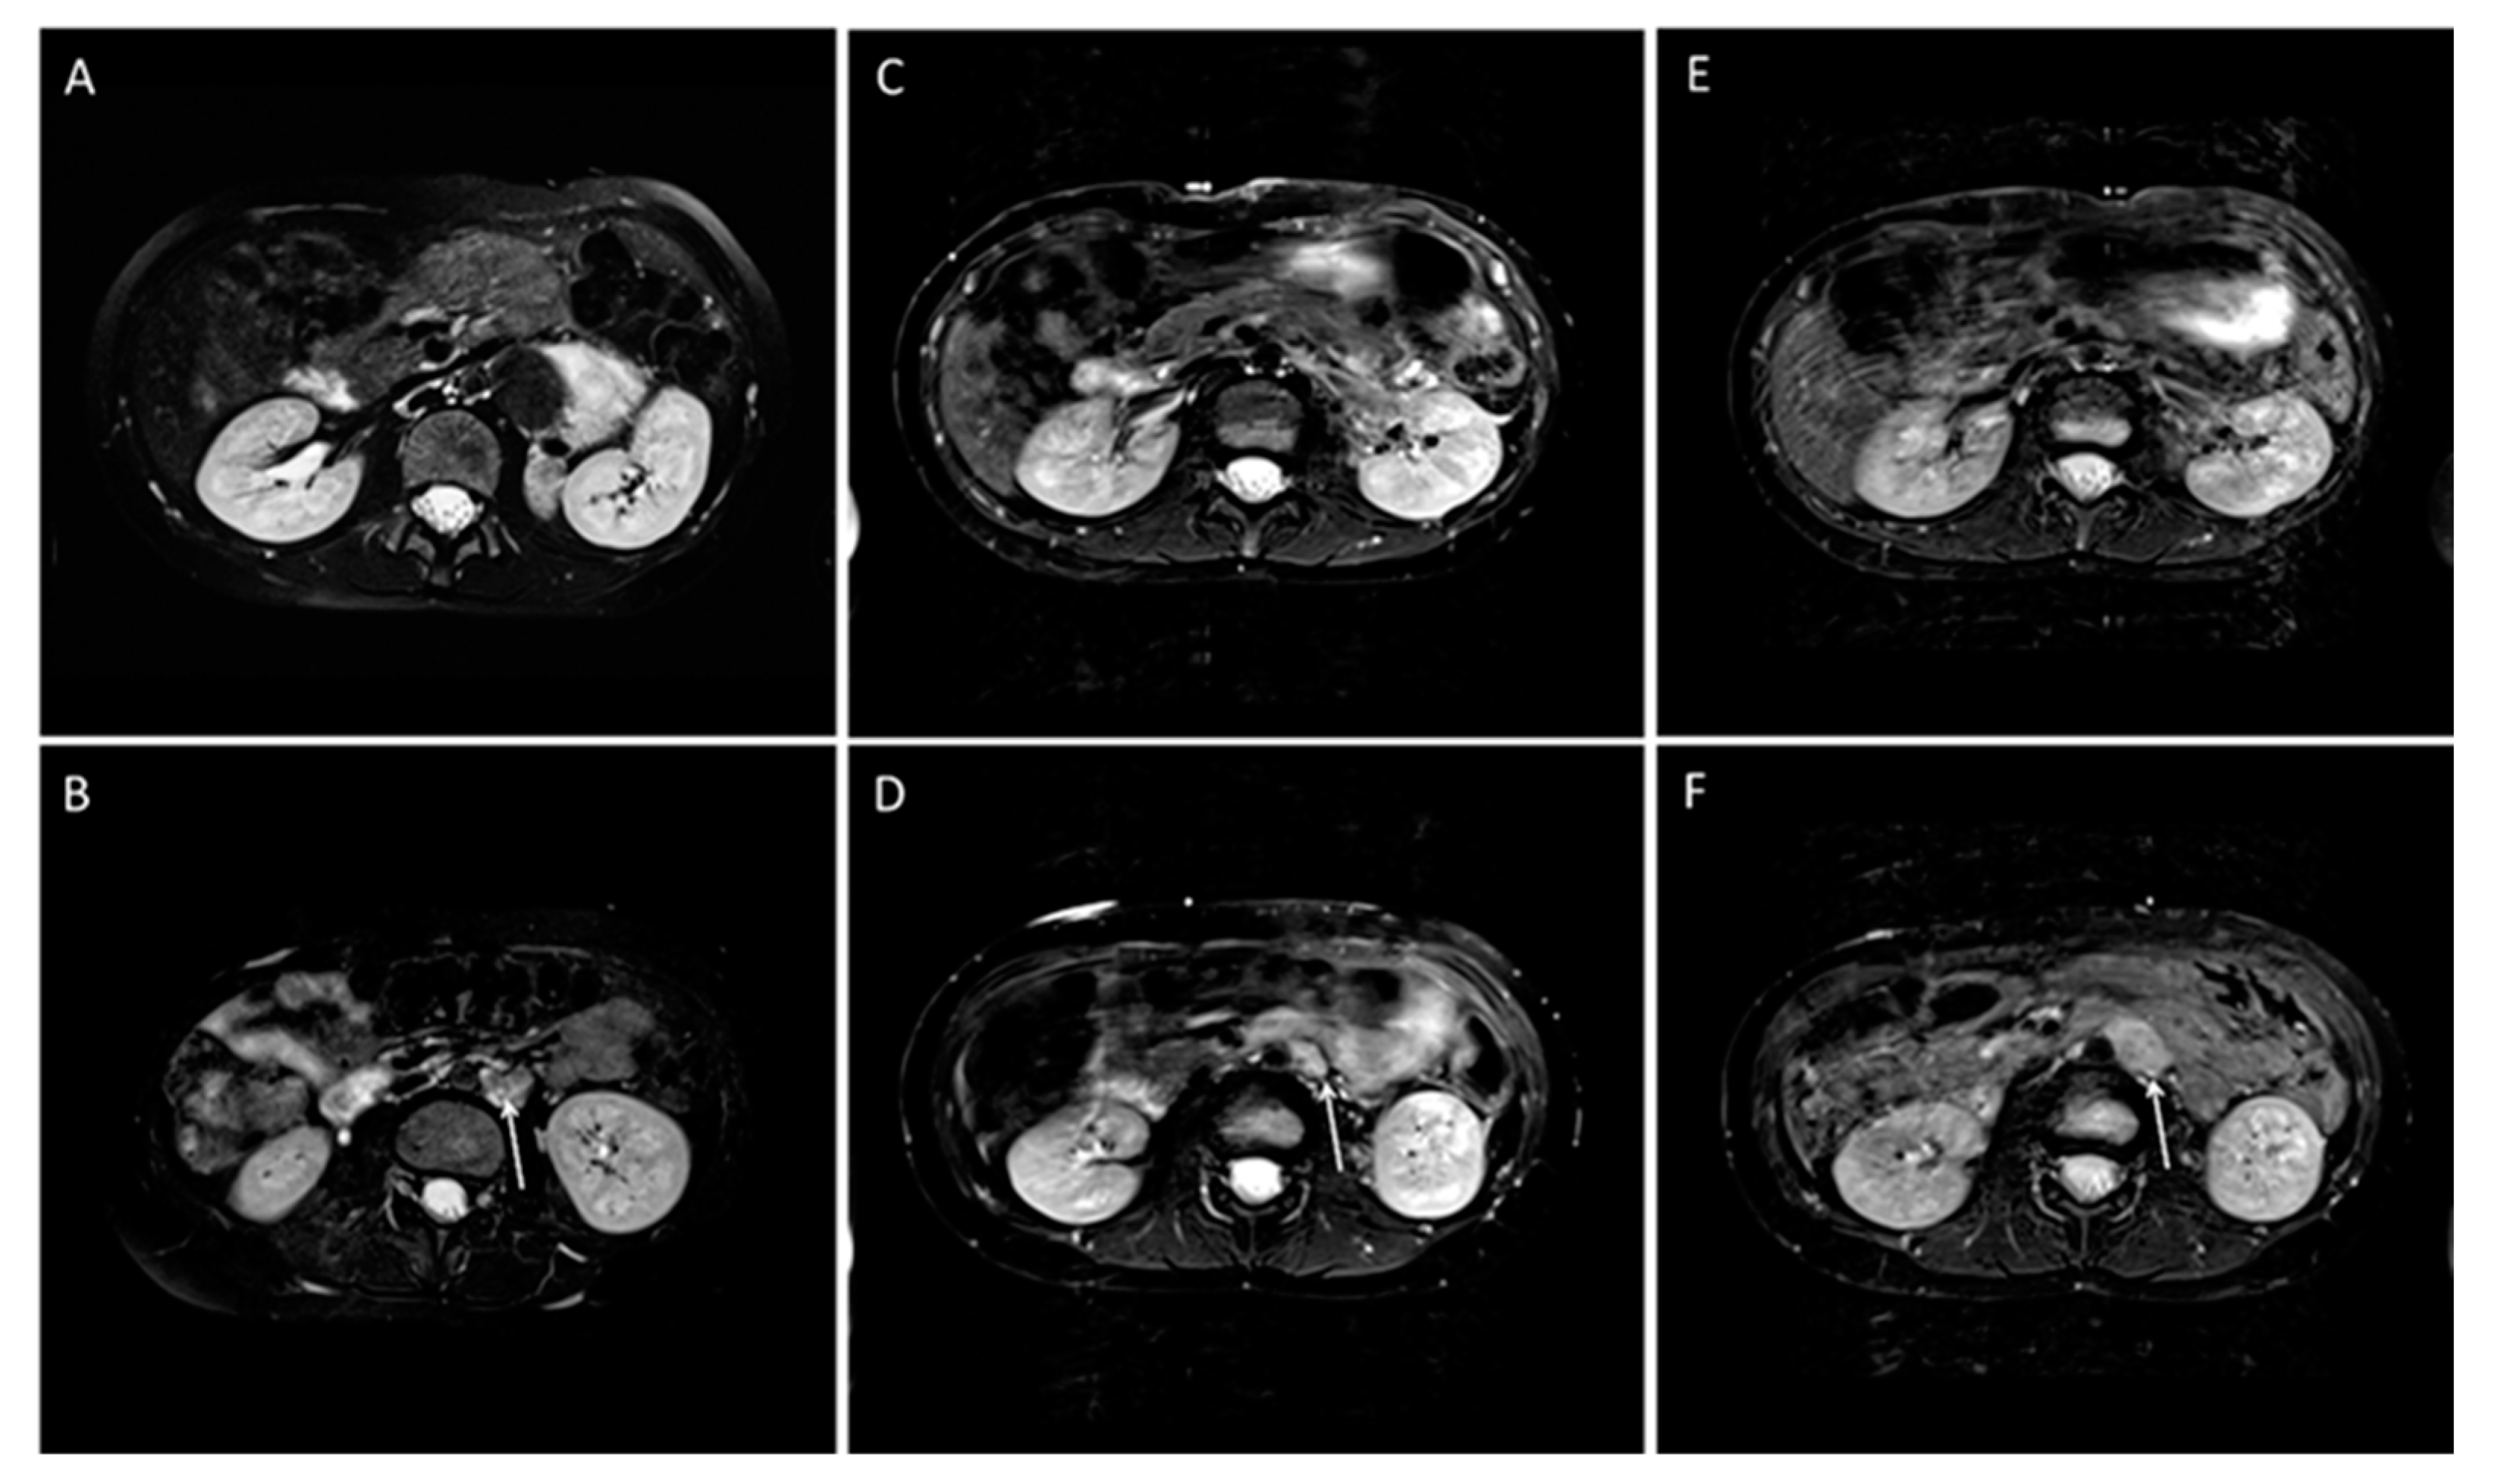

- Gassenmaier, S.; Tsiflikas, I.; Maennlin, S.; Urla, C.; Warmann, S.W.; Schaefer, J.F. Retrospective accuracy analysis of MRI based lesion size measurement in neuroblastic tumors: Which sequence should we choose? BMC Med. Imaging 2020, 20, 105. [Google Scholar] [CrossRef] [PubMed]

- Gassenmaier, S.; Tsiflikas, I.; Fuchs, J.; Grimm, R.; Urla, C.; Esser, M.; Maennlin, S.; Ebinger, M.; Warmann, S.W.; Schafer, J.F. Feasibility and possible value of quantitative semi-automated diffusion weighted imaging volumetry of neuroblastic tumors. Cancer Imaging 2020, 20, 89. [Google Scholar] [CrossRef]

- Neubauer, H.; Li, M.; Muller, V.R.; Pabst, T.; Beer, M. Diagnostic Value of Diffusion-Weighted MRI for Tumor Characterization, Differentiation and Monitoring in Pediatric Patients with Neuroblastic Tumors. Rofo 2017, 189, 640–650. [Google Scholar] [CrossRef]